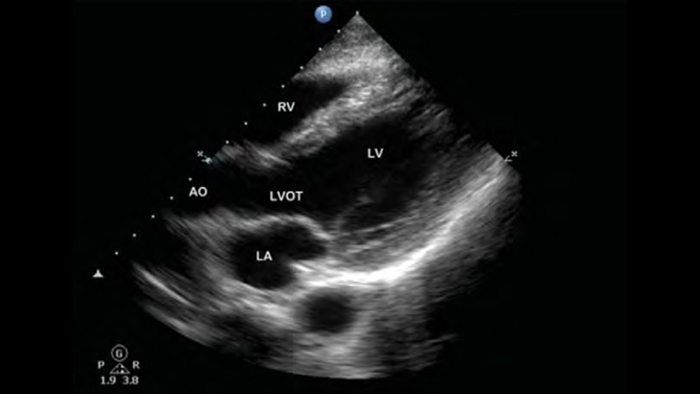

Lumify handheld ultrasound for anesthesiology helps you clearly visualize border definition with your needle placement, surrounding nerves, vessels and fascial planes.

Lumify helps you clearly visualize needle placement, surrounding nerves, vessels and fascial planes.